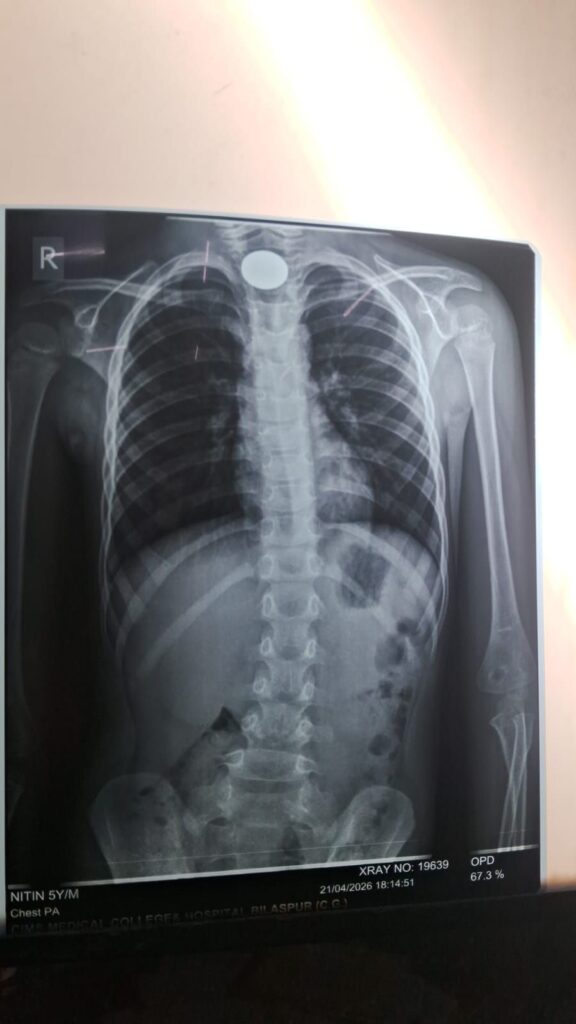

बिलासपुर। छत्तीसगढ़ आयुर्विज्ञान संस्थान (सिम्स) ने एक बार फिर आपात चिकित्सा में अपनी दक्षता साबित की है। महज 5 वर्षीय मासूम नितिन सिंह की जान समय रहते एंडोस्कोपिक तकनीक से बचा ली गई। खेलते-खेलते बच्चे द्वारा निगला गया 5 रुपए का सिक्का उसके गले में इस तरह फंस गया था कि उसकी सांसें थमने लगी थीं, लेकिन सिम्स की विशेषज्ञ टीम ने त्वरित कार्रवाई कर उसे सुरक्षित बाहर निकाल लिया।

सोमवार शाम करीब 7 बजे धवलपुर (थाना झगड़खा, जिला चिरमिरी) निवासी नितिन सिंह ने खेलते समय 5 रुपए का सिक्का निगल लिया। सिक्का श्वसन मार्ग के पास फंस गया, जिससे बच्चे को सांस लेने में गंभीर दिक्कत होने लगी। परिजन बिना समय गंवाए उसे सिम्स लेकर पहुंचे, जहां डॉक्टरों ने तत्काल स्थिति की गंभीरता को समझते हुए इमरजेंसी उपचार शुरू किया।

बच्चे को तुरंत ऑपरेशन थिएटर में शिफ्ट कर एंडोस्कोपिक तकनीक से उपचार किया गया। इस आधुनिक प्रक्रिया में बिना किसी बड़े चीरे के विशेष उपकरणों की मदद से गले में फंसे सिक्के को सावधानीपूर्वक बाहर निकाला गया।